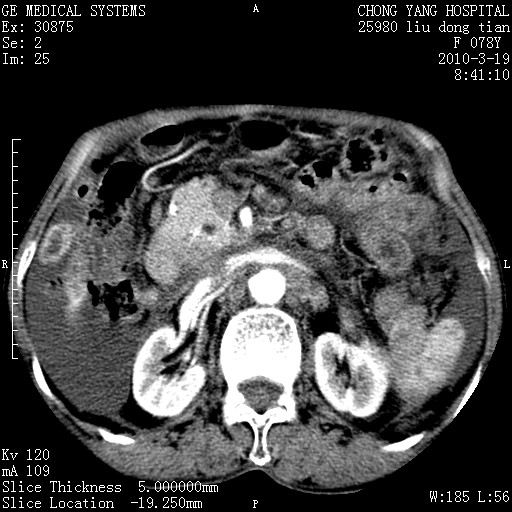

标题: CT25199:F 78Y 腹胀半年 消瘦乏力 [打印本页]

胆囊壁增厚并明显强化,胆囊癌伴多发转移瘤可能性大,淋巴瘤不除外,右肾囊肿,胸腹水.

考虑nhl,肝、脾、腹膜腔及腹膜后多发淋巴结受侵,腹水,右肾囊肿,慢性胆囊炎,右侧少量胸腔积液。

胰头有肿块形成,胰头ca伴肝脾、腹膜腹膜后转移

胆囊有软组织影有强化,支持胆囊癌,肝脾、腹膜后淋巴结转移。

nhl的淋巴结多围绕主动脉,而且主动脉会移位,所以不考虑nhl。

分开来讲:肝左叶、尾叶病灶有不均强化像肝癌;

脾脏病灶无强化,像多发囊肿或淋巴管瘤,不除外淋巴瘤(低强化);

胆囊增生性病变:胆囊癌,腺肌增生症,慢性胆囊炎;

肝门、胰腺头、腹膜后多个团块: 淋巴瘤,转移;

腔静脉肝内段细小有无布加可能?

一元论最好了 淋巴瘤所致改变; 胆囊癌转移不像,胆囊周围肝组织清晰,肝癌淋巴结转移?三元论都不止。

最后报的胰头癌多发转移,脾脏单独考虑囊肿或淋巴管瘤。